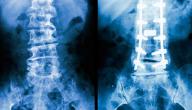

• تثبيت الفقرات: وتتضمن هذه العملية دمج فقرتين أو أكثر من فقات العمود الفقري بشكل دائم، وذلك لتعزيز استقرار الحالة المرضية التي يعاني منها الشخص أو لتصحيح التشوه أو لتخفيف الألم، وعادة ما يقوم الجراحون باستئصال جزء عظمي يُدعى الطّعم من عظم الورك أو الحوض ووضع هذا الجزء بين الفقرتين المراد تثبيتهما، فهذا الأمر يتسبب بتشكيل جزء عظمي متكامل على شكل فقرة واحدة كبيرة، وفي كثير من الحالات، يستخدم الجراح الأسلاك والأربطة والبراغي والصفائح لتثبيت الفقرات يدويًا لإعطاء المريض الاستقرار الفوري قبل أن تلتحم الفقرتين بنمو الطعم بينهما.